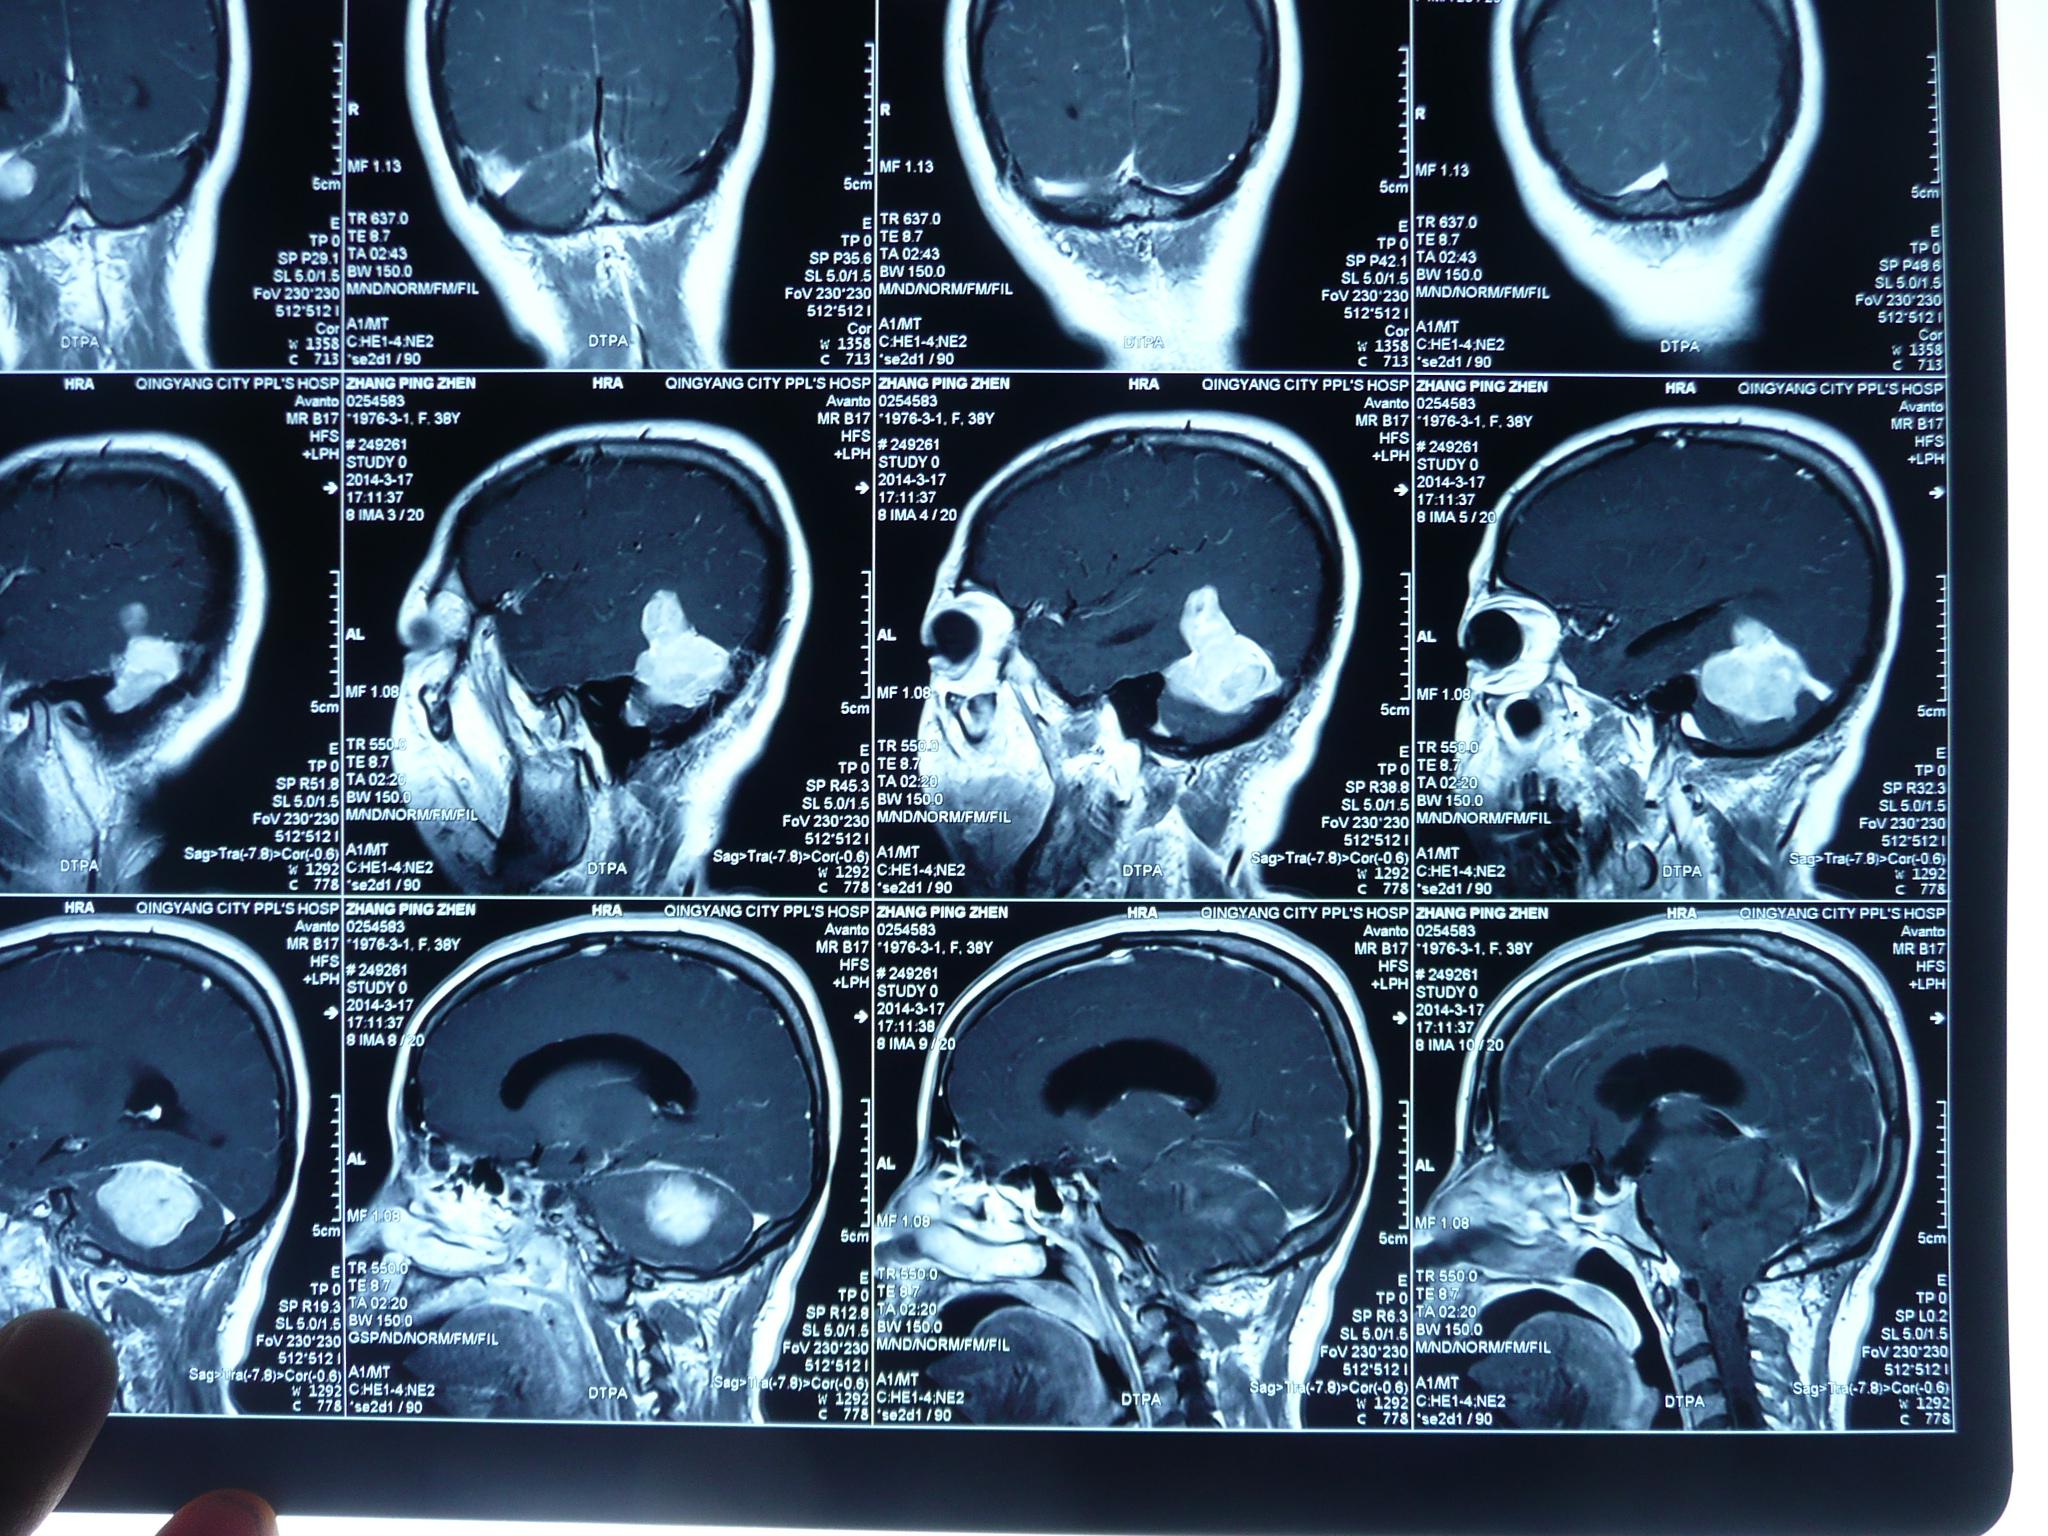

贺晓生教授小脑幕上下骑跨脑膜瘤的外科切除手术案例 - 好大夫在线

原创贺晓生教授小脑幕上下骑跨脑膜瘤的外科切除手术案例

贺晓生教授小脑幕上下骑跨脑膜瘤的外科切除手术案例